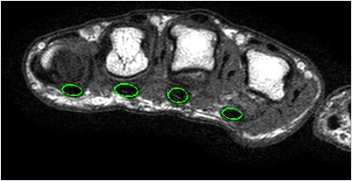

Due to surgical needs and the promotion of minimally invasive orthopedic techniques, our team designed a set of surgical instruments suitable for minimally invasive trigger finger surgery. Besides addressing the issue of poor clinical treatment outcomes through minimally invasive concepts and specially designed instruments, it also allows for the complete removal of the annular tendon sheath using specialized instruments, facilitating histological examination and medical imaging analysis. Furthermore, through biomechanical and hand functional assessments, long-term prognostic follow-up of patients is conducted, exploring the effectiveness of rehabilitation interventions for patients with more severe disease progression. In addition, our team uses cadaveric human hand samples to investigate the characteristics of the annular tendon sheath and flexor tendons from a mechanical and material property perspective, integrating this information with clinical assessment and imaging analysis results to explore the etiology and assist in future clinical diagnosis and intervention. Our team has also established a biomechanical model of the hand based on the mechanical, imaging and clinical parameters obtained in previous studies for future hand research. We have also developed an "integrated trigger finger percutaneous dissection surgery simulation training system" to create a virtual surgical training system. This training system will allow more surgeons to practice and become familiar with the operation of minimally invasive surgical techniques, thereby improving the quality of clinical medical care.